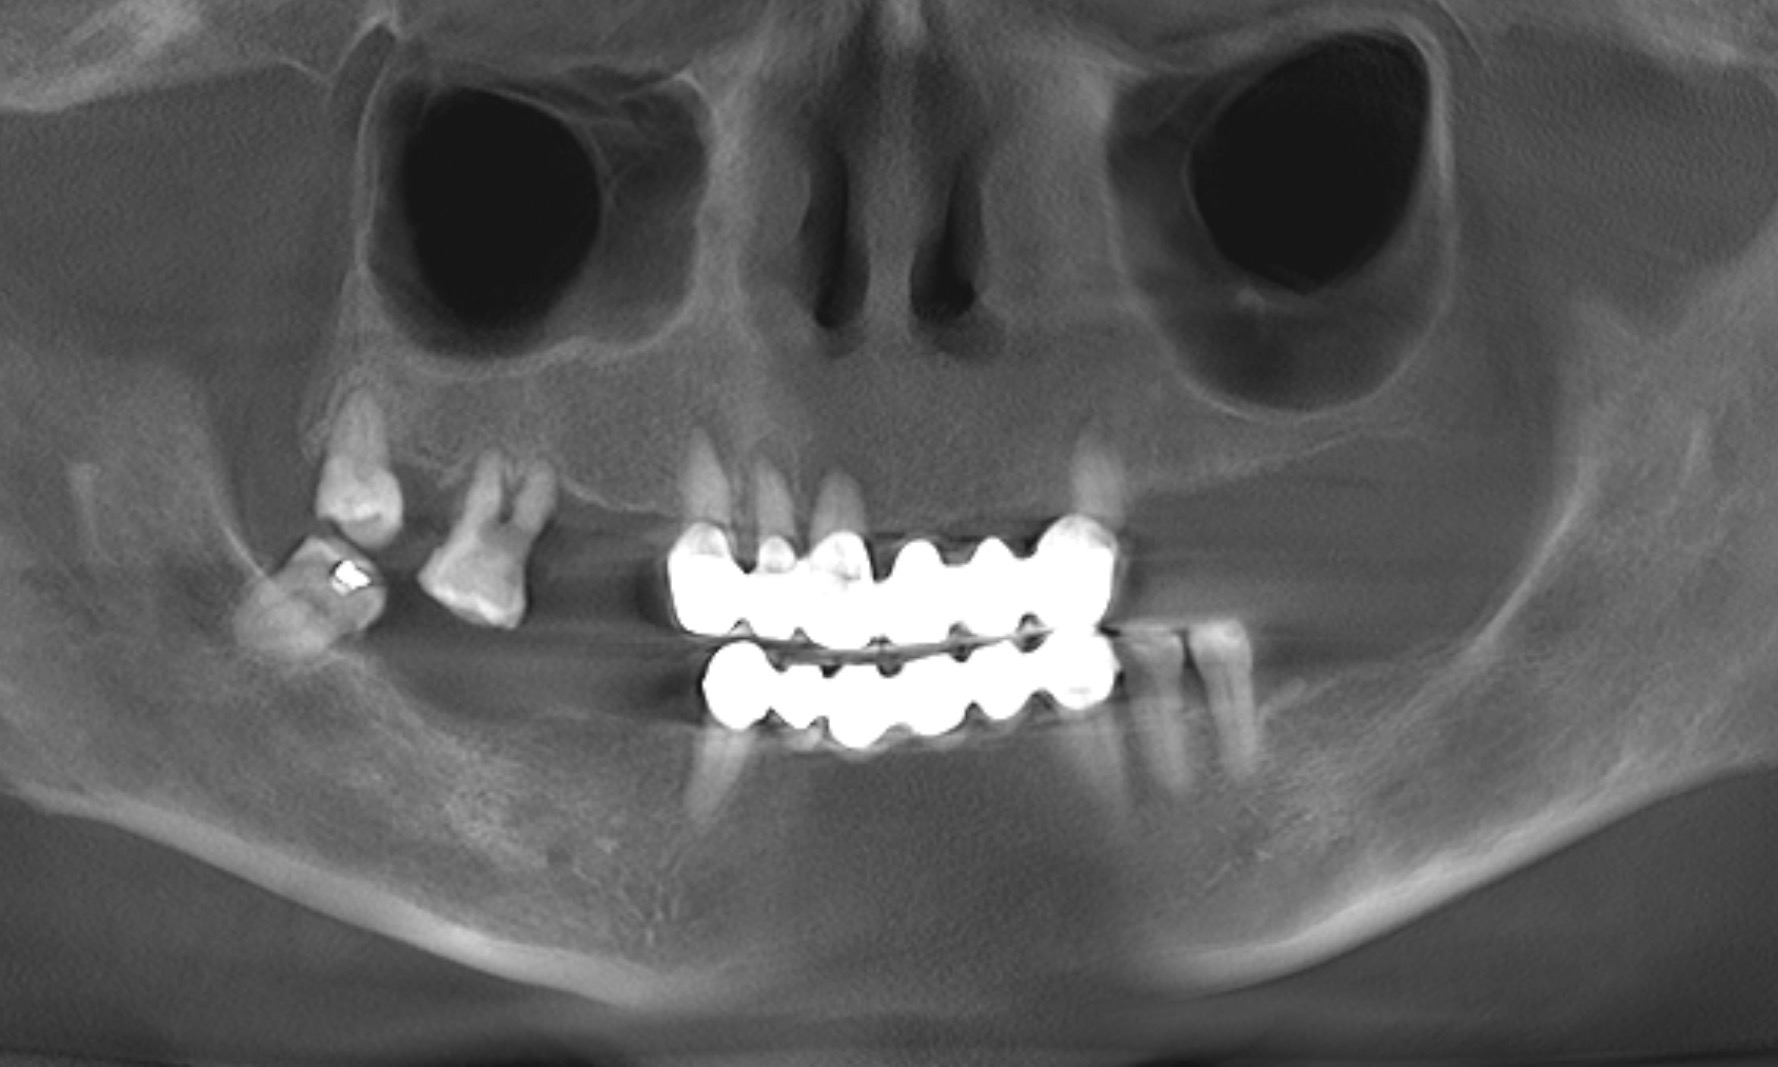

The extra-oral examination showed a low smile line, and the intra-oral examination found a removable bridge from tooth #13 to tooth #23 that was poorly adapted and showed signs of deterioration. The maxillary teeth, with the exception of tooth #18, were mobile. Generalised gingival inflammation, bleeding on probing and dental caries were also present (Fig. 1). The radiographic examination exposed severe bone loss in the posterior of the maxillary left quadrant, as well as caries and apical lesions on maxillary teeth (Fig. 2).

After conducting both radiographic and clinical assessments, the patient was categorised as having a complex condition according to both the surgical and prosthodontic SAC classifications. This classification system, developed by the International Team for Implantology, assists in evaluating the level of challenge and potential complications linked to implant-related restoration (Fig. 3).